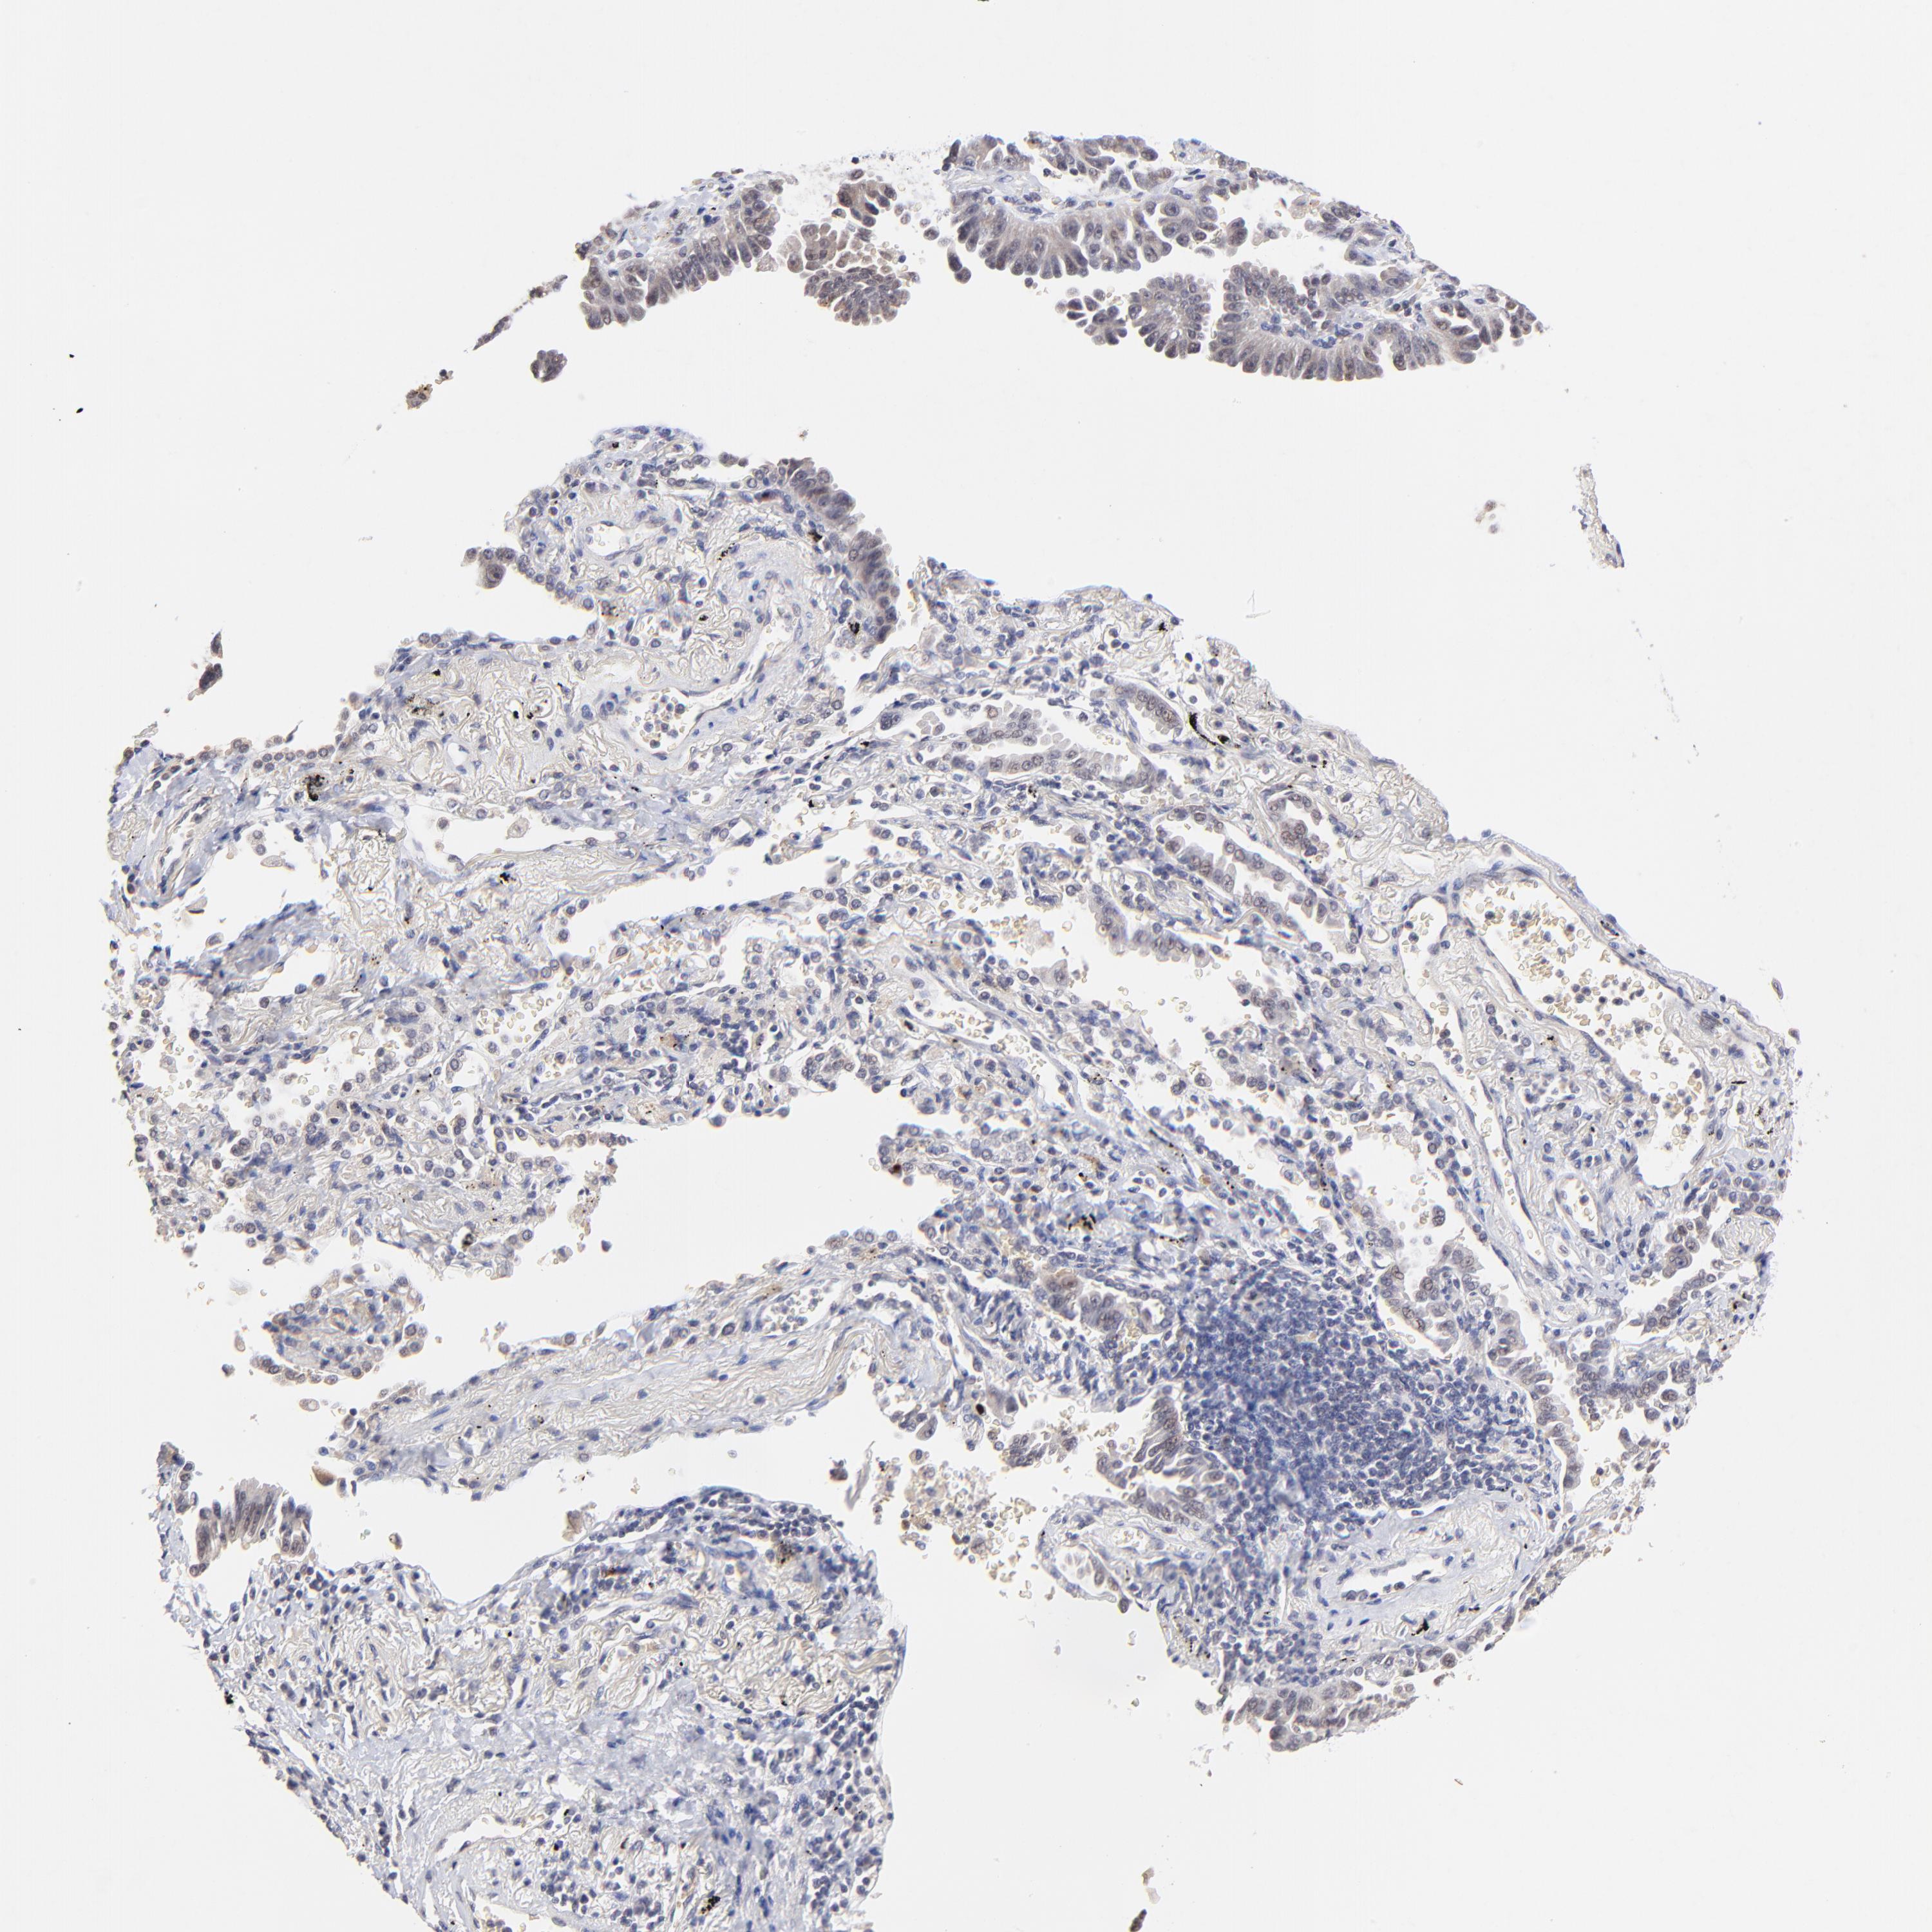

CANCER LUNG CANCER Show tissue menu

LUAD TCGA LUAD VALIDATION LUSC TCGA LUSC VALIDATION PROTEIN LUAD CPTAC PROTEIN LUSC CPTAC PROTEIN EXPRESSION

Lung cancer

Human cancer

LUNG ADENOCARCINOMA (TCGA) - Interactive survival scatter ploti

The Survival Scatter plot shows the clinical status (i.e. dead or alive) for all individuals in the patient cohort, based on the same data that underlies the corresponding Kaplan-Meier plots. Patients that are alive at last time for follow-up are shown in blue and patients who have died during the study are shown in red.

The x-axis shows the expression levels (FPKM) of the investigated gene in the tumor tissue at the time of diagnosis. The y-axis shows the follow-up time after diagnosis (years). Both axes are complimented with kernel density curves demonstrating the data density over the axes. The top density plot shows the expression levels (FPKM) distribution among dead (red) and alive patients (blue). The right density plot shows the data density of the survived years of dead patients with high and low expression levels respectively, stratified using the cutoff indicated by the vertical dashed line through the Survival Scatter plot. This cutoff is automatically defined based on the FPKM cutoff that minimizes the p-score. The cutoff can be changed by dragging the vertical line or by entering a cutoff value in the square labeled "Current cut-off".

Under the Survival Scatter plot the p-score landscape (black curve; left axis) is shown together with dead median separation (red curve; right axis). Dead median separation is the difference in median mRNA expression between patients who have died with high and low expression, respectively. It is calculated as follows: median FPKM expression of dead patients with high expression - median FPKM expression of dead patients with low expression. This is intended to aid the user in visually exploring custom cutoffs and the associated p-scores and dead median separation.

Individual patient data is displayed and can be filtered by clicking on one or more of the category buttons on the top of the page. Categories describing expression level and patient information include: high, low, alive, dead, female, male and tumor stages. The scale of the x-axis can be toggled between linear and log-scale by clicking on the "x log" button. Mouse-over function shows TCGA ID, patient information and mRNA expression (FPKM) for each patient.

& Survival analysisi

Kaplan-Meier plots summarize results from analysis of correlation between mRNA expression level and patient survival. Patients were divided based on level of expression into one of the two groups "low" (under cut off) or "high" (over cut off). X-axis shows time for survival (years) and y-axis shows the probability of survival, where 1.0 corresponds to 100 percent.

ZNF559-ZNF177 is not prognostic in Lung Adenocarcinoma (TCGA)

TCGA RNA samplesi

RNA-seq data is reported as average FPKM (number Fragments Per Kilobase of exon per Million reads), generated by the The Cancer Genome Atlas (TCGA) .

Normal distribution across the dataset is visualized with box plots, shown as median and 25th and 75th percentiles. Points are displayed as outliers if they are above or below 1.5 times the interquartile range. FPKM values of the individual samples are presented next to the box plot.

Average pTPM 0.5

Number of samples 497